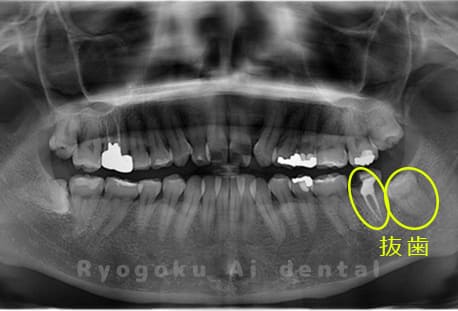

Case14

- 重度カリエス、親知らず

- 治療内容

- 親知らずの抜歯、移植手術、マイクロエンド、ダイレクトボンディング

- 治療費用

- 220,000円

他院で親知らずと共に抜歯と診断された患者様です。親知らずの抜歯の必要性と左下奥歯の保存を試みた場合、歯の状態から根管治療、歯周外科、補綴の必要性から、移植治療を選択されました。大きな問題もなく、治療後も経過良好です。

<リスク・副作用>

治療後、痛みや違和感、出血、腫れなどが出る事があります。喫煙者、糖尿病などの方の場合、歯が生着しない場合があります。